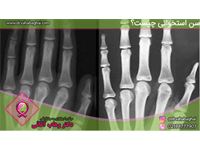

جستجو کلمه جستجو جستجو گروه بندی همه موارد مقالات » رادیولوژی از تاریخ تاریخ صحیح نمی باشد. * تا تاریخ تاریخ صحیح نمی باشد. * رادیولوژی چیست؟ رادیولوژی چیست و چه کاربردهای تشخیصی و درمانی دارد؟ و معرفی انواع دستگاههای آن. سن استخوانی شما چقدر است؟ امروزه یکی از مواردی که به کمک آن سن را ارزیابی میکنند، سن استخوانی است.